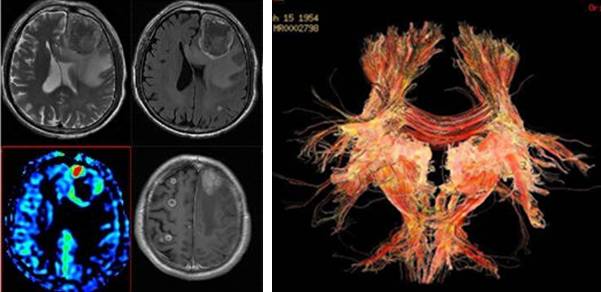

脑功能成像——3D-ASL和DTI

3D-ASL优势:

1.我院为美国GE公司3T MR机型,其3D-ASL为最新3D- ASL技术,有FDA认证,安全可靠;

2.3D-ASL可获得CBF定量信息,单位:ml/min.100g;

3.采用FSE序列,利用螺旋K空间填充技术,为最新的准连续式动脉自旋转标记技术;

4.对比度及信噪比均明显增高,运动伪影明显减少。

DTI技术是研究复杂脑组织结构的一种无创的有力工具。它在神经解剖、纤维连接和大脑发育方面应用前景广阔, 对于神经系统疾病和脑功能研究有巨大的潜在优势。随着技术的提高和更好的后处理分析, DTI会更加广泛、更加可靠的应用于研究和临床工作中。